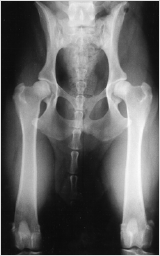

1. Distraktion

Die Hintergliedmaße des Hundes werden in einer neutralen, das Gelenk belastenden Position gelagert. Ein spezielles Instrument wird genutzt, um den angeborenen Spielraum der Hüfte festzustellen. Dieses PennHIP exklusive Verfahren erlaubt eine exakte, reproduzierbare Messung der "Lockerheit" der Hüfte